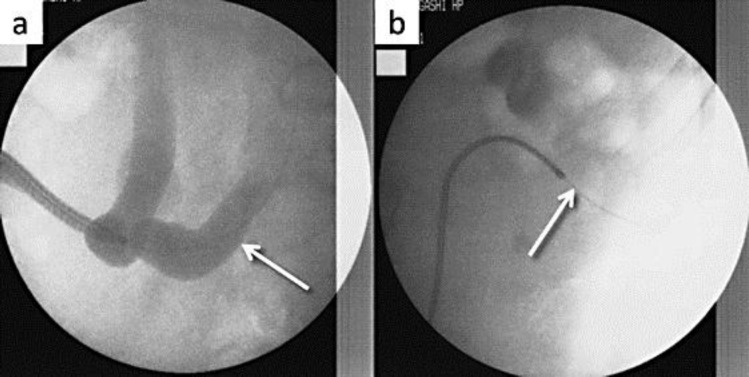

A 33-year-old male with an ileal conduit was referred to our department for the treatment of left renal calculi. After inserting a ureteral access sheath, a ureteroscopy-assisted retrograde nephrostomy was made. Percutaneous nephrolithotomy was successfully achieved using this nephrostomy.